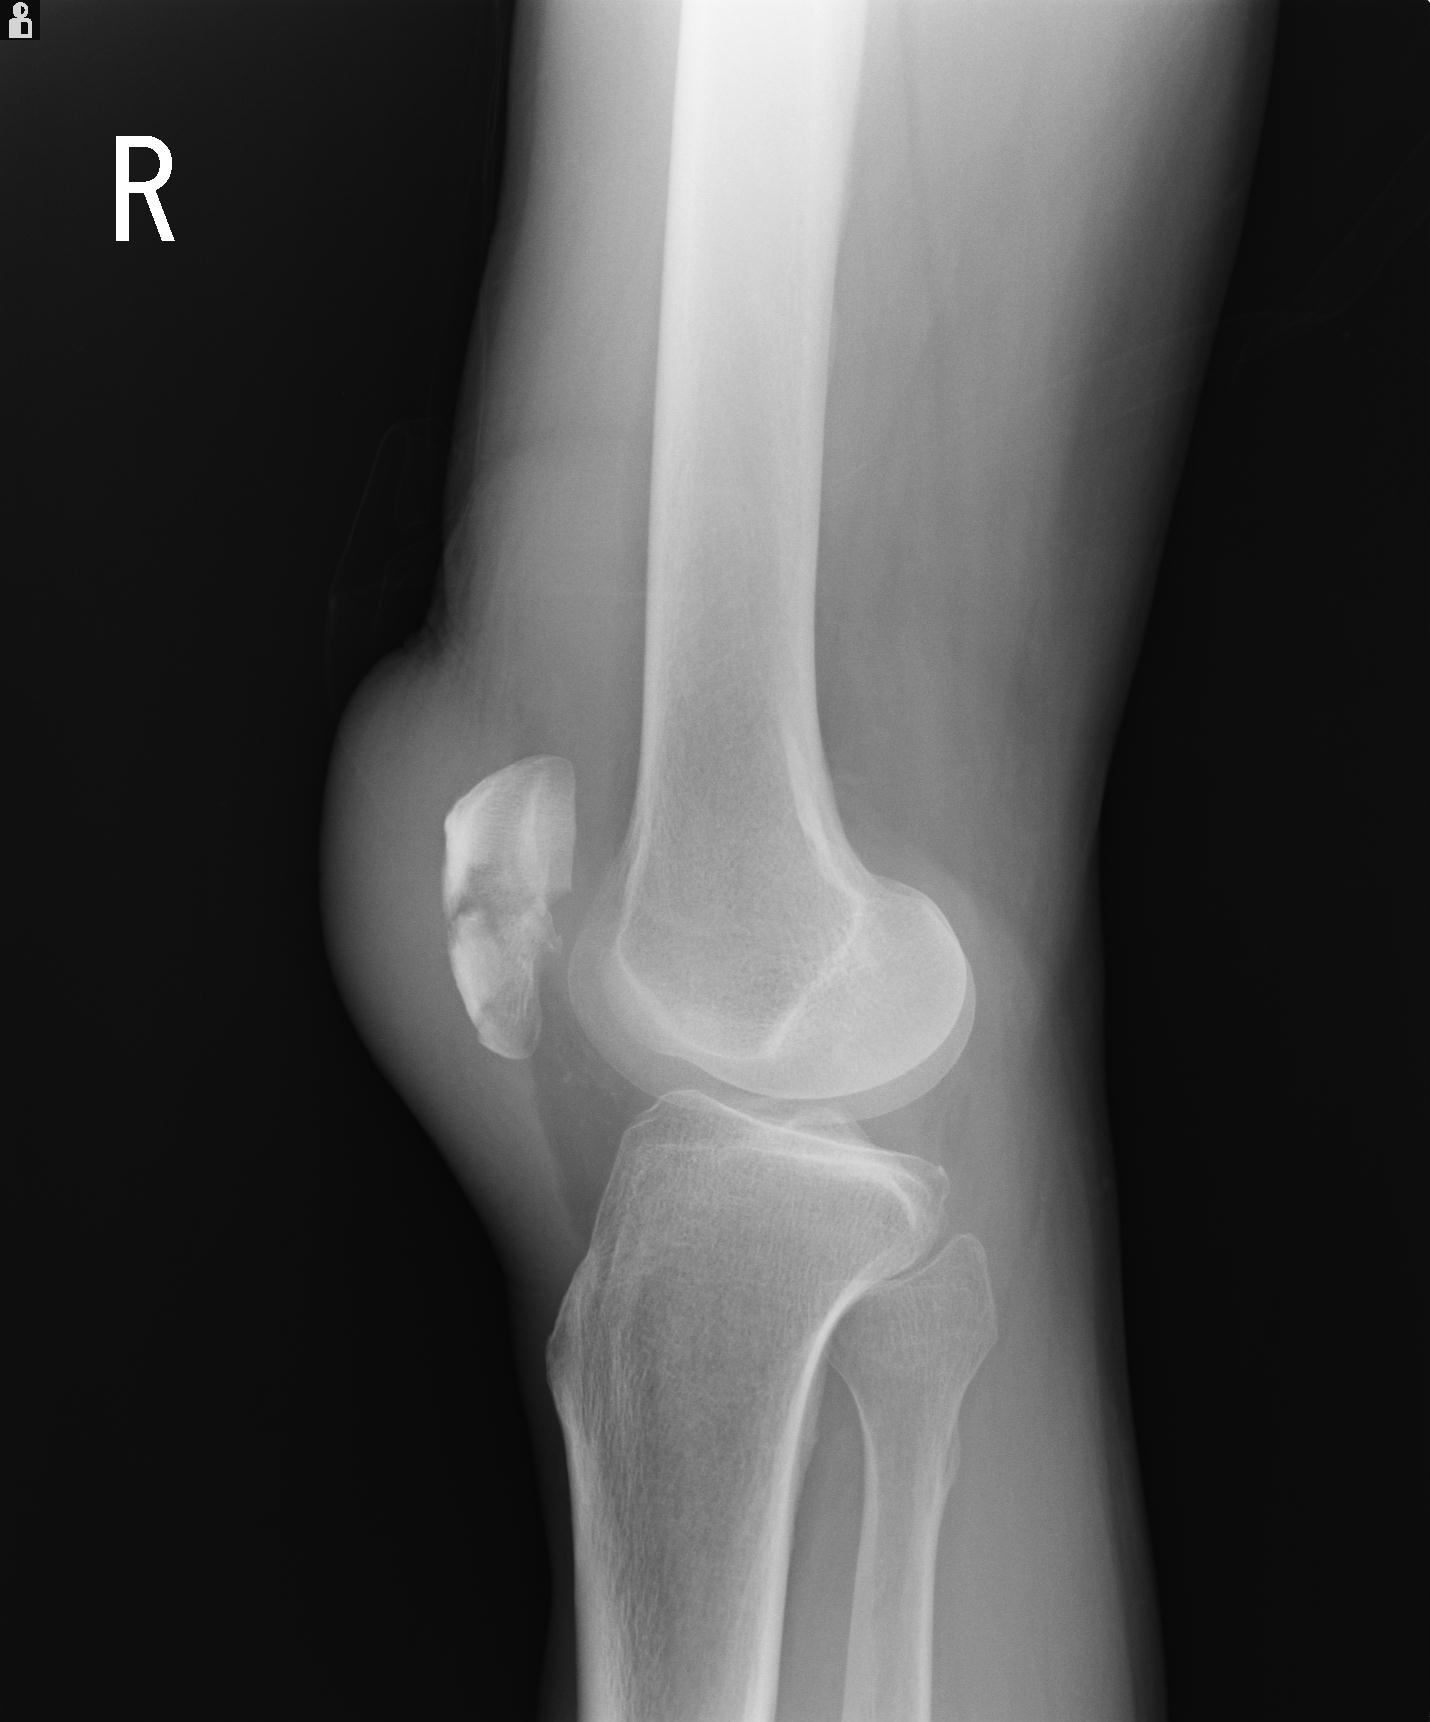

49554 3/13 膝 4R 3/16 4R 1/18 2R 78歳男性 膝蓋骨骨折